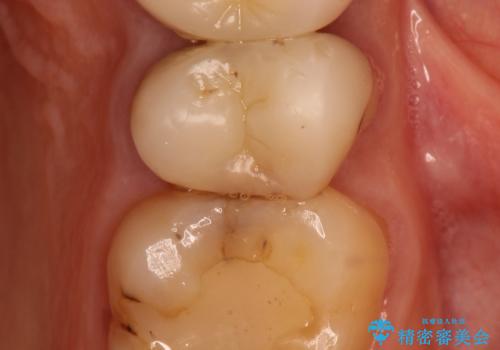

過去に治療してあった左上の歯が一部欠けていました。

かぶせ物と詰めてある修復物を除去すると歯肉の中まで虫歯になっていました。